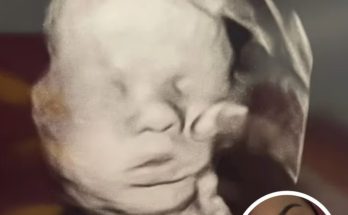

Pregnant Mom Prays For Her Baby’s Health, Stunned When She Looks Closer At Ultrasound – Tiny House Zone

July 16, 2025July 16, 2025 - by Chris Taylor - Leave a Comment

Note: we are republishing this story which originally made the news in May 2025. In a moment both tender and mysterious, a Kentucky mother is sharing what she believes to …